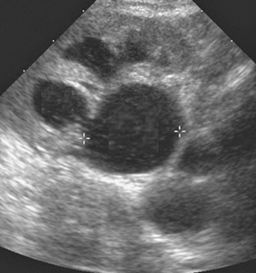

Vous hospitalisez le patient et mettez en place un monitoring cardio-tensionnel et un traitement associant insuline-glucose par voie intraveineuse (IV) et bêta-2 mimétique en aérosol. Vous réalisez une échographie qui retrouve une dilatation pyélocalicielle du rein gauche (image ci-contre), ainsi qu’une radiographie de thorax qui retrouve une surcharge modérée. La biologie de contrôle retrouve une kaliémie à 4,7 mmol/L et une créatininémie à 627 μmol/L.